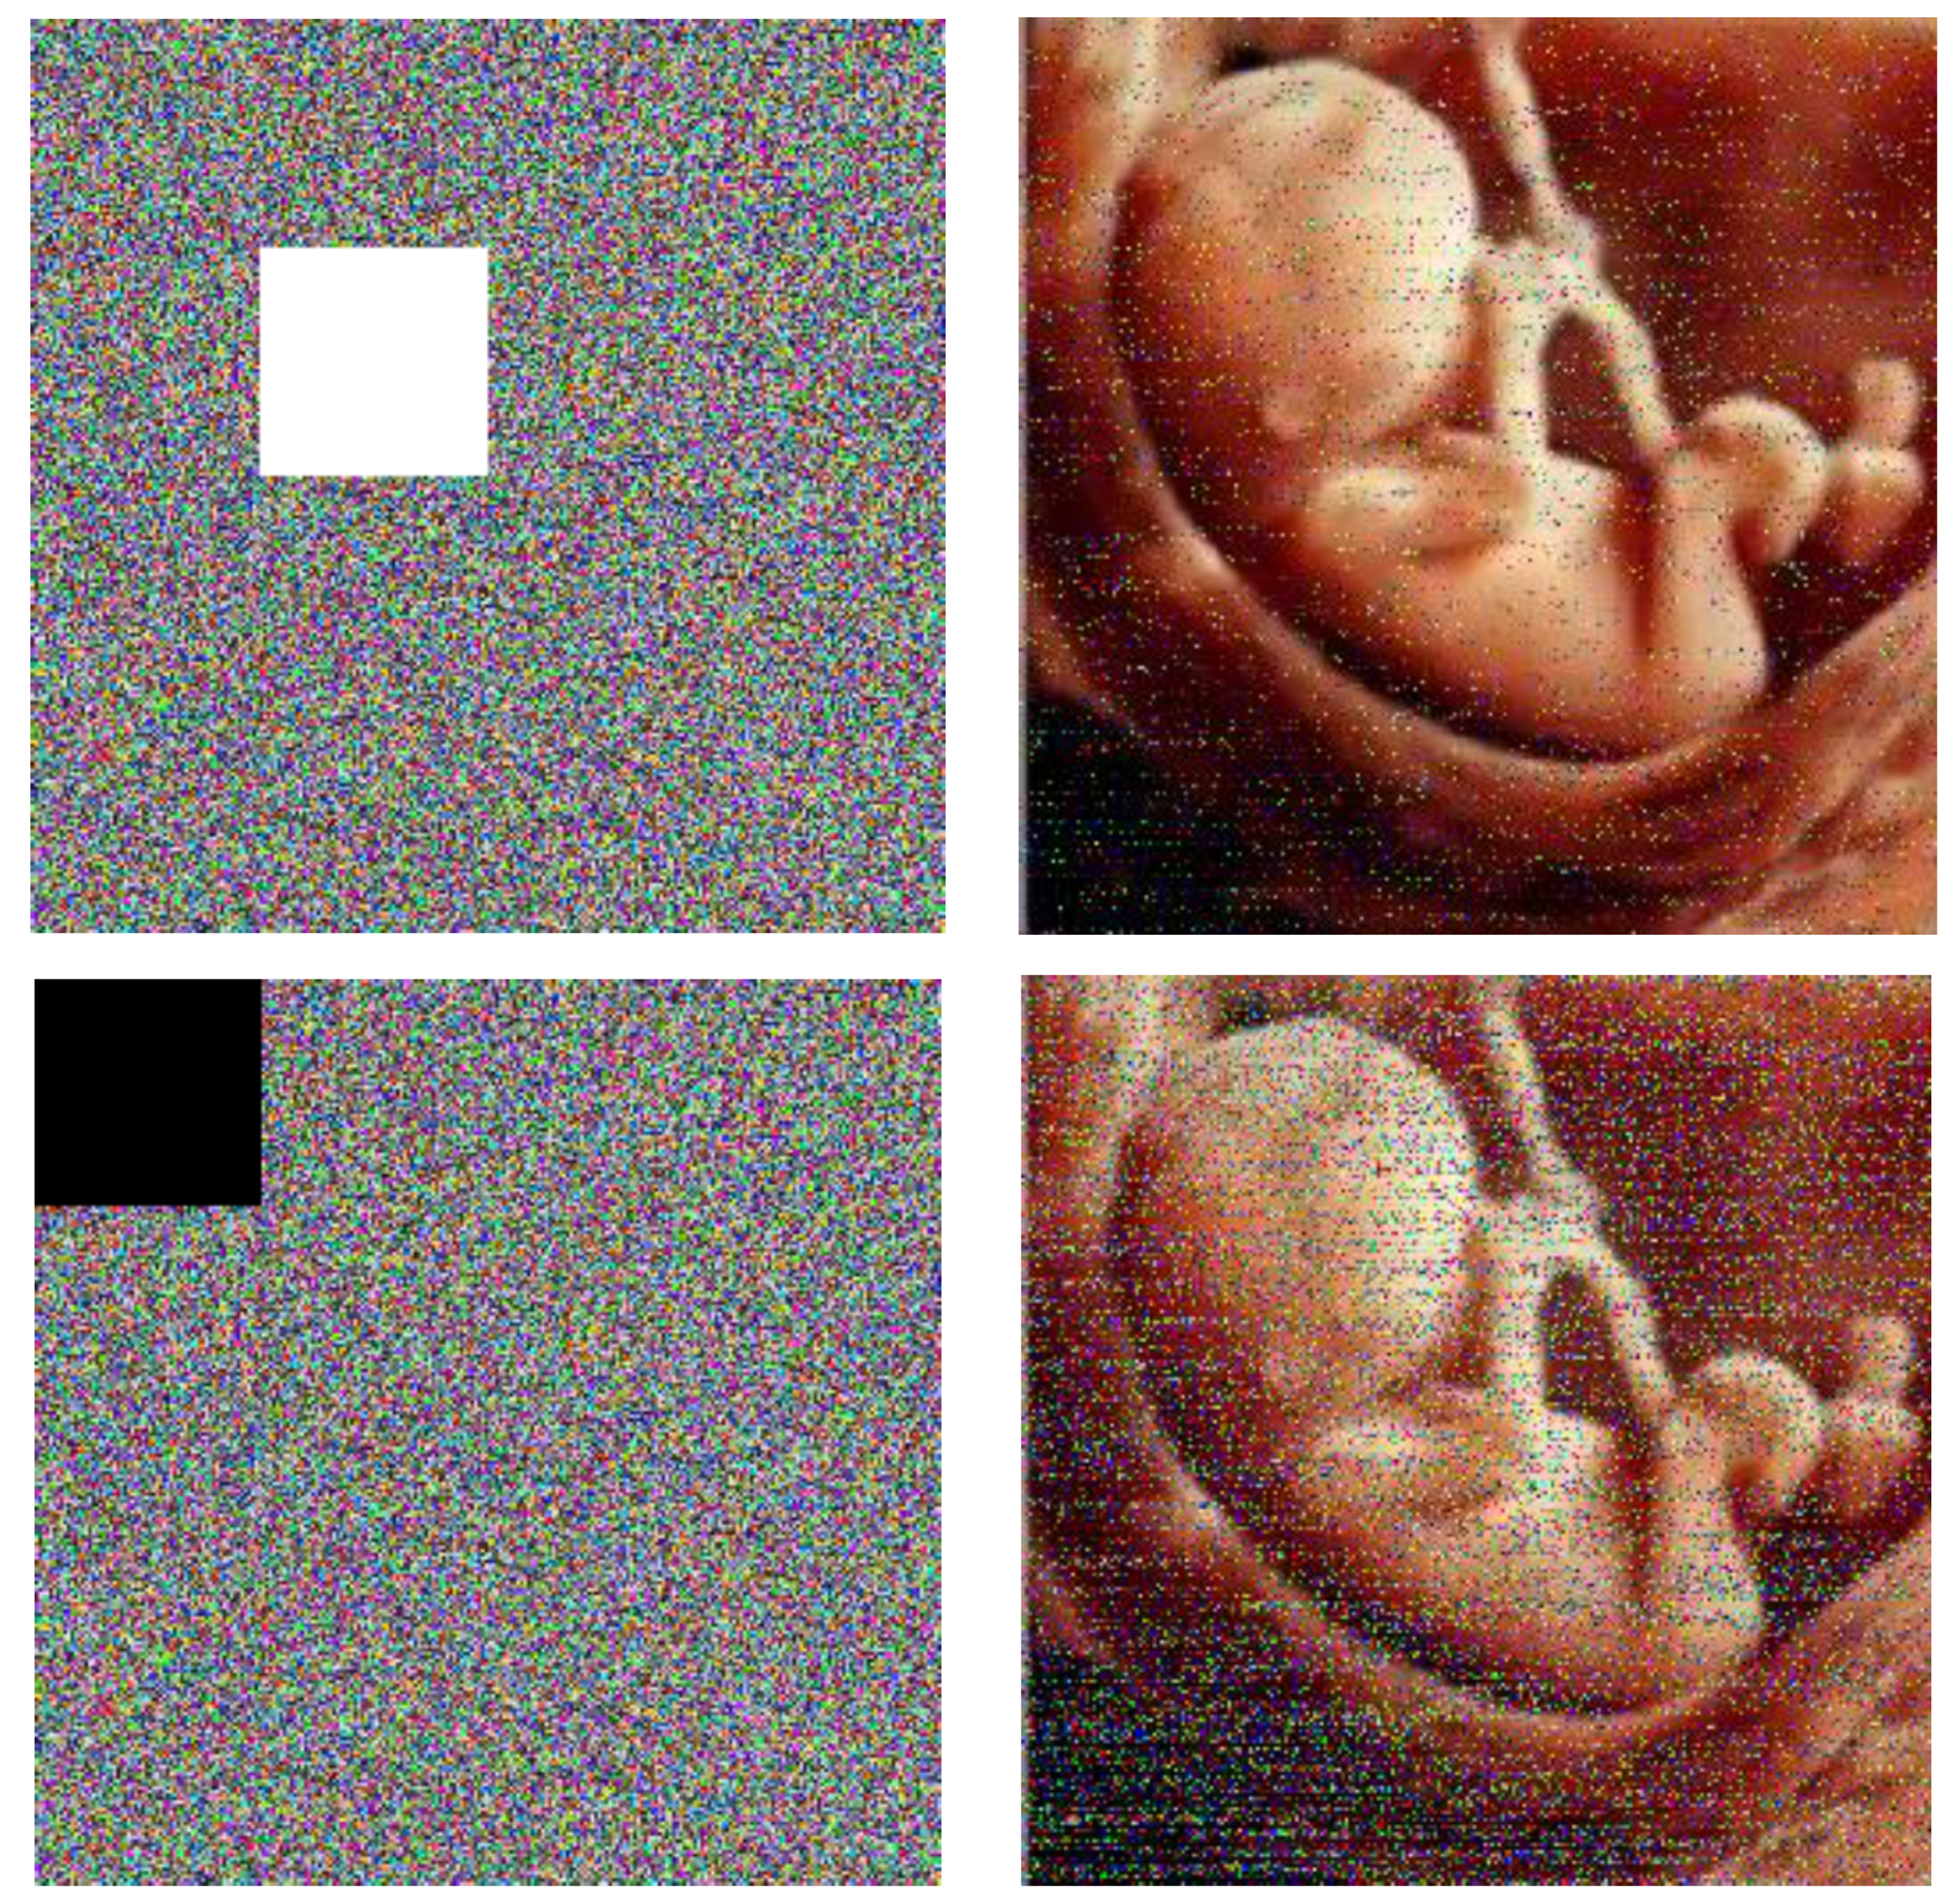

For example, four color images 256 × 256 in size have been selected as the plain images. In Figure 3, images b, e, h, and k are images that are encrypted by the proposed algorithm for the plain images a, d, g, and j, respectively; and images c, f, i, and l are the decrypted images.

Figure 3.

(a,d,g,j): Plain images. (b,e,h,k): Respective encrypted images. (c,f,i,l): Respective decrypted images. Initial values for all images: (a0 = 0.1314, b0 = 0.5214, c0 = 0.3698, and d0 = 0.8419). Values of the chaotic system: Image (a): sha256 = ‘9ADBBFB88CFD90C23CE114E47402054E6DDC4182510E80980EA7151CD11E6D18’, image (d): sha256 = ‘8BF6A886E4B58D2B530749EE9BAB54A3C360D406DC5B901CC169D7870FA3CA09’, image (g): sha256 = ‘49A22186DB65786789CD1391CDE4D9737039E758F39A45C59D8338DE05353337’, and image (j): sha256 = ‘6EB1ADE45F27A67E09A25265835F05BC11E057255DA81359299631F4724936C8’.